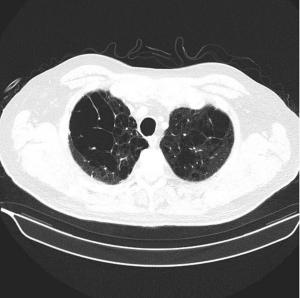

The mediastinal benign schwannomas is a nerve sheath tumor composed of Schwann cells. These tumors are often asymptomatic and found incidentally.

Two weeks after injury to the right chest wall and shoulder, the patient continues to have pain. He also reports numbness and tingling in his hands bilaterally. What do the ED images reveal?